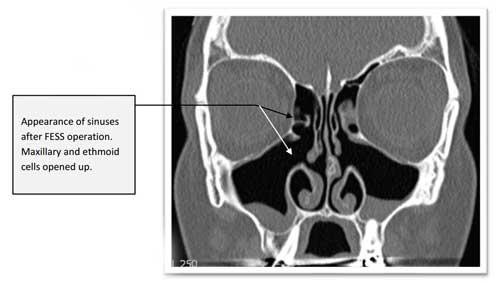

nasal sinuses CT of nasal polyps CT of normal sinuses CT after removal of polyps Removing nasal polyps is actually quite straightforward, however reducing the chances of them returning is quite a lot harder. Generally ‘polypectomy’ can just mean removing the bulk of the polyps allowing improved breathing, but there is a significant chance that they will grow back even with steroid sprays. Clearing out polyps from their ‘roots’ and opening up these areas so steroid sprays prevent polyps from growing back has been shown to reduce the chance of the polyps growing back. Avoiding multiple operations is something Mr Vik Veer is very keen on, and he will advise you on the various options for nasal polyps. The most important thing to remember is that the polypectomy operation does not ‘cure’ polyps, it merely cleans them out temporarily. The vast majority of patients will need steroid sprays to avoid another operation again. Prof Vik Veer uses medication before any procedure to try and avoid surgery if at all possible, and there are a number of therapies that may help with nasal polyps.